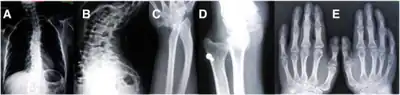

(A) AP plain X-ray of the spine demonstrating dorsal and lumbar scoliosis. (B) Lateral plain X-ray of spine showing severe lumbar lordosis. (C) X-ray film of right forearm evidencing distal bowing of the radius. (D) AP plain X-ray film of right forearm showing radius dislocation and radial-cubital dissociation. (C) AP plain X-ray film of hands demonstrating short 4th and 5th metacarpals.